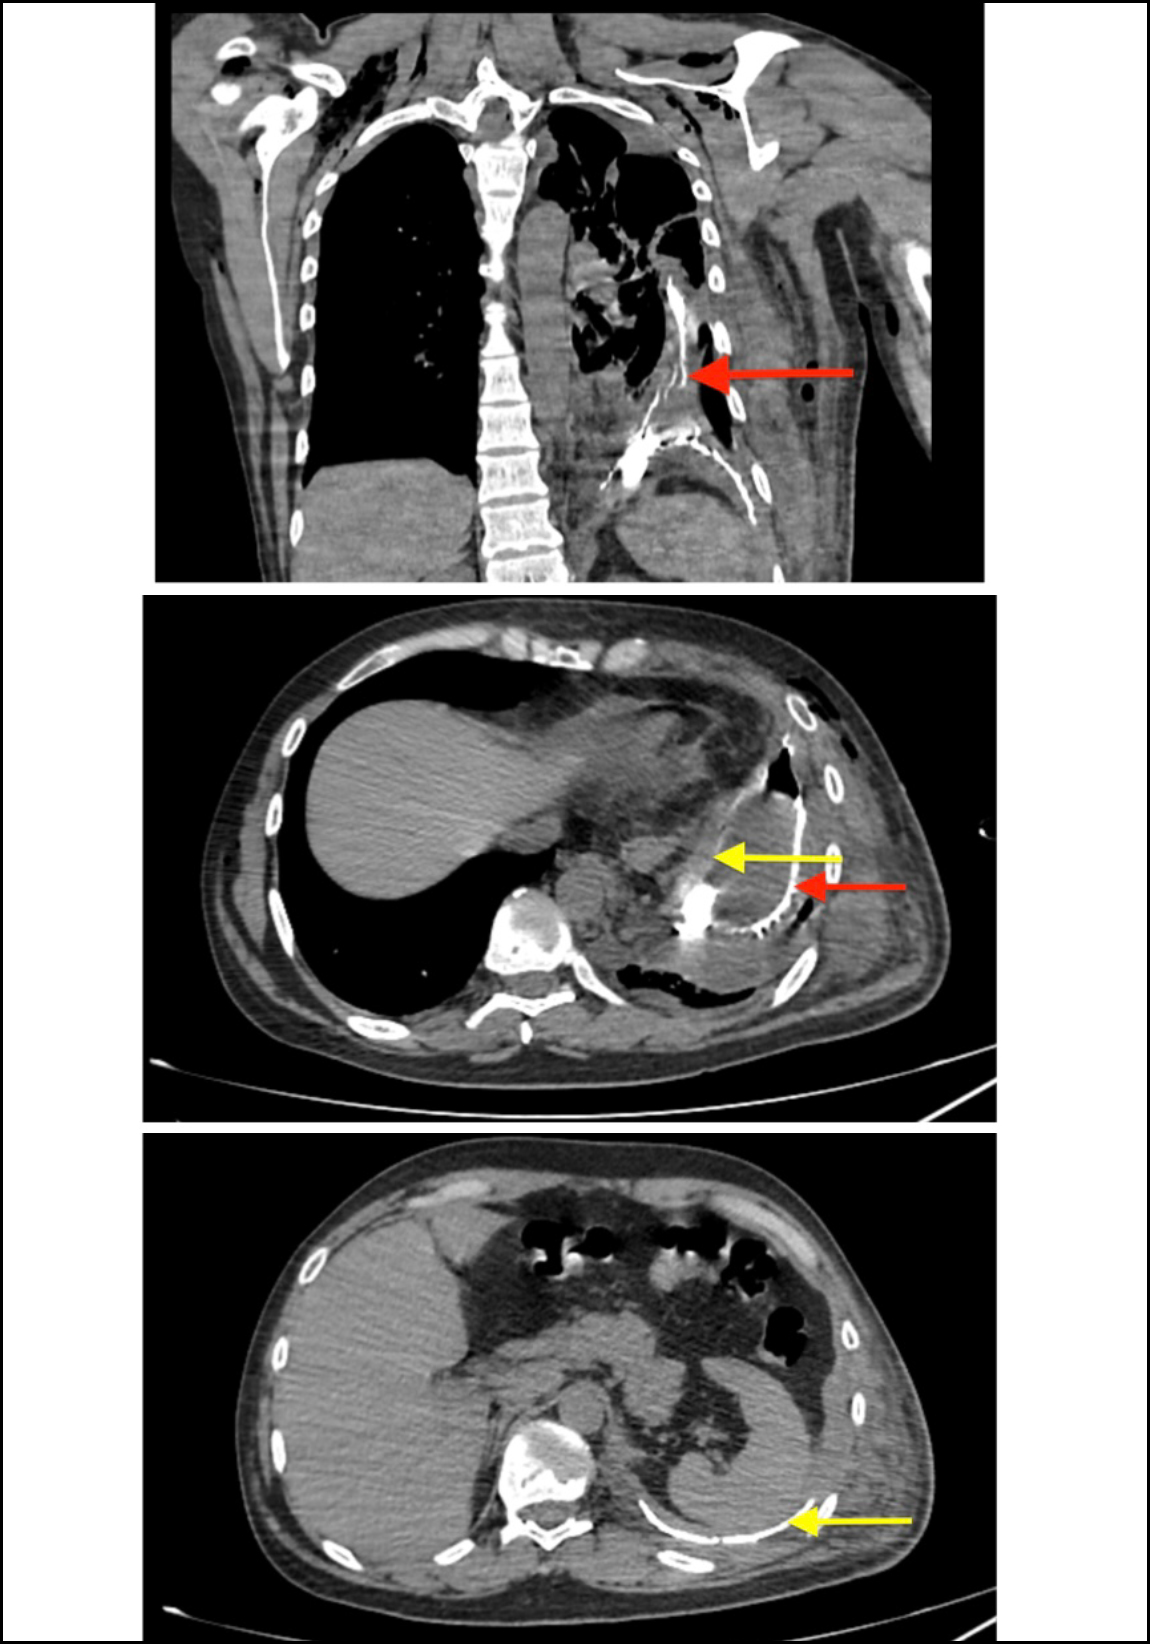

Initial clinical improvement was noted following chest tube insertion. However, soon after initiation of oral feed, food particles were noted in the drain. Barium swallow suggested GPF and diaphragmatic rupture (Figure 1). Computed tomography (CT) of the chest and abdomen revealed a large left pleural collection with air-fluid levels, discontinuity in the gastric fundus, and direct communication with the pleural space (Figure 2). No other intra-abdominal injuries were seen.

Figure 2: Preoperative CT with oral contrast only: coronal and axial CT demonstrated oral contrast in pleural space (red arrow), identification of a diaphragmatic defect (yellow arrow) with associated herniation of the stomach into pleural space, consistent with gastropleural fistula.